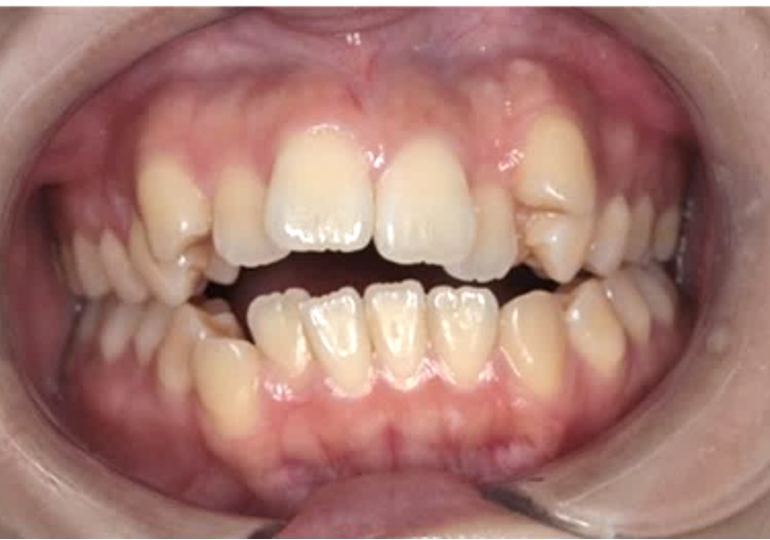

乱杭歯(叢生)・八重歯

歯並びがデコボコに並んでいる状態を「叢生(そうせい)」といいます。

また上の犬歯が唇側(外側)に出ているものを、「八重歯」と呼びます。

八重歯は、日本では好意的に捉えることもありますが、欧米ではマイナスの印象を与えるようです。歯が並ぶ場所(骨の大きさ)に対して、歯が大きいときに起こりやすく、歯ブラシが届きにくいため汚れやむし歯のリスクが高まります。

重なった部分にむし歯ができると、治療が困難なため、短期的に再治療が必要になってしまうケースがあります。